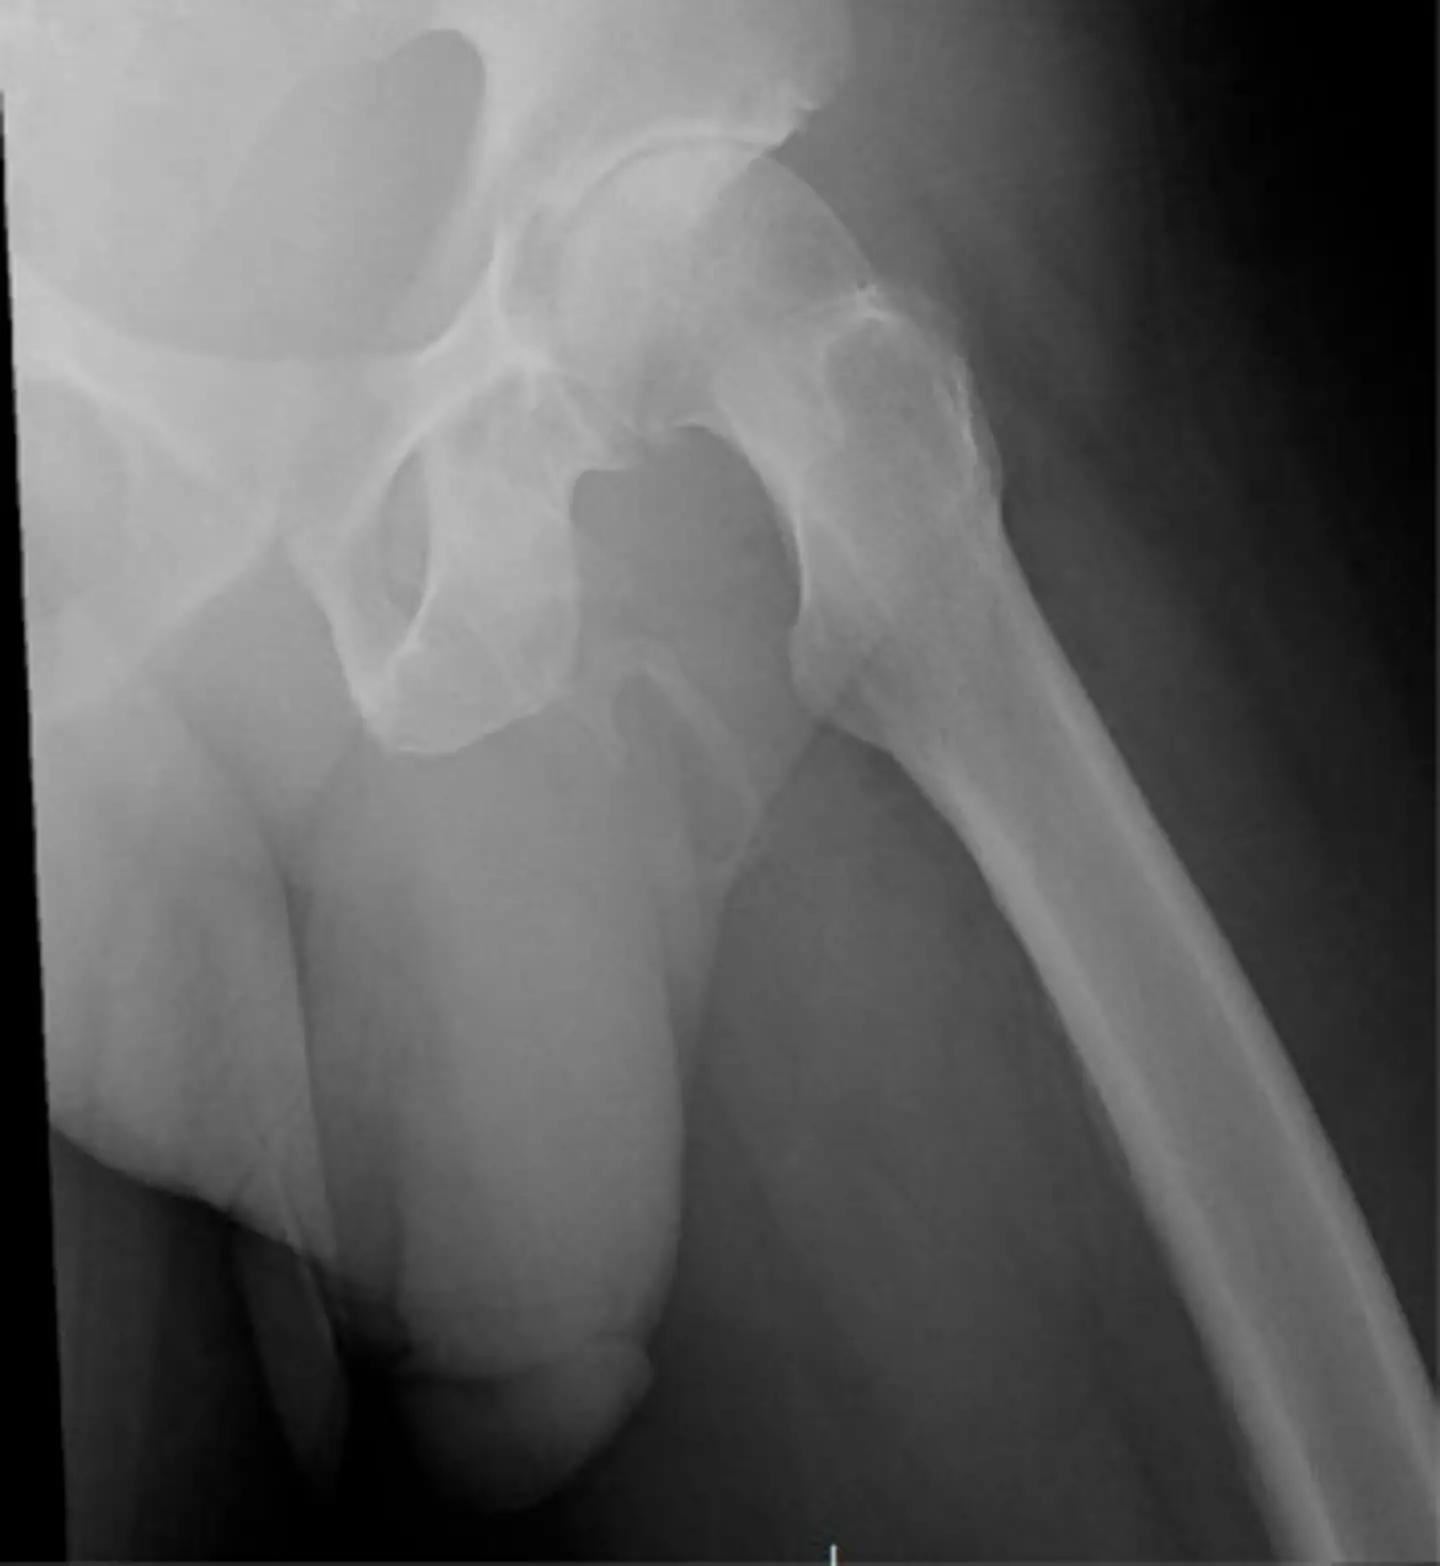

As per the Urology Case Report, the man's 'physical exam was negative except for a penile pain', sparking him to undergo an x-ray 'to rule out any fracture showed a severe, asymmetric degenerative changes of the right hip'.

The patient went on to be diagnosed with penile ossification - an extremely rare condition with fewer than 40 cases reported.

Penile ossification occurs when calcium salts build up in the soft tissue of the penis, forming extraskeletal bone.